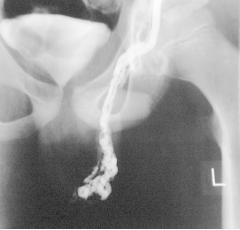

睾丸囊肿造影图片